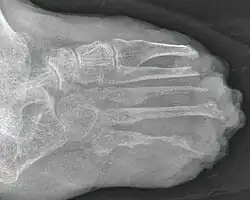

Leprafuß

Röntgenaufnahme des Fußes